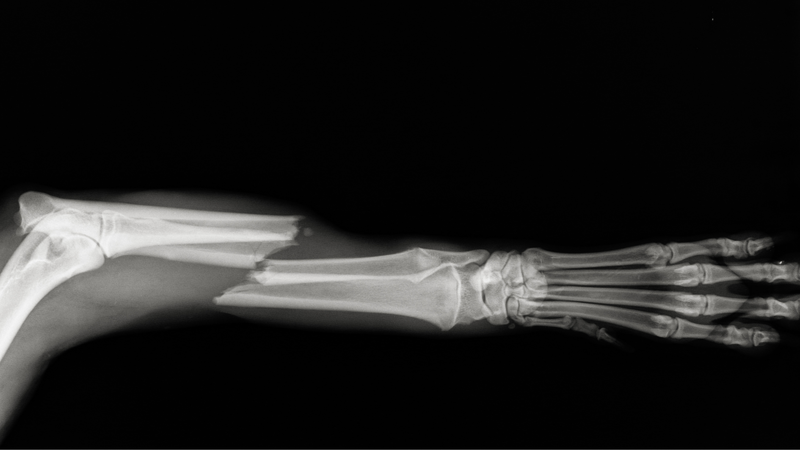

Trong số các xương trong chi trên của cơ thể, xương cánh tay (humerus) là xương có kích thước lớn nhất. Đầu trên của xương cánh tay nối liền với bả vai (scapula), trong khi phần đáy của xương cánh tay kết nối với hai xương cẳng tay (ulna và radius) thông qua khớp khuỷu (elbow joint). Cấu trúc này giúp hỗ trợ và làm cho vùng vai và cẳng tay trở nên linh hoạt, cho phép chúng ta thực hiện các cử động đa dạng.

Đây là một trong những chấn thương phổ biến, thường do tai nạn giao thông, té ngã, va chạm với bề mặt cứng và các nguyên nhân khác. Ngoài ra, gãy xương cánh tay cũng có thể do các bệnh lý như nang xương, u xương. Đa số các trường hợp gãy xương cánh tay ở vị trí này đều phức tạp, có thể là gãy xương hở và thường đi kèm với triệu chứng đau, sưng, bầm tím ở vùng cánh tay, cùng với giới hạn chuyển động ở vị trí này.